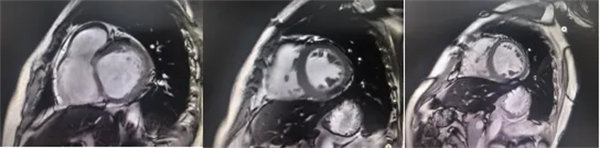

在常規(guī)心臟MRI檢查中,醫(yī)學(xué)影像科發(fā)現(xiàn)患者心肌異常表現(xiàn),考慮鐵過(guò)載性心肌病,為明確診斷要進(jìn)一步加做鐵定量技術(shù),加掃T2 mapping序列。CMR鐵定量技術(shù)是目前評(píng)估心肌鐵含量的“金標(biāo)準(zhǔn)”,能夠快速、無(wú)創(chuàng)、精準(zhǔn)量化心肌內(nèi)鐵沉積程度,檢查結(jié)果提示患者局部心肌T2*值顯著低于正常范圍,符合鐵過(guò)載性心肌病的診斷標(biāo)準(zhǔn)。

基底部、中間部及心尖部 局部心肌T2*值明顯減低T2* 10-20/s, 部分小于10/s

心肌信號(hào)局部減低 呈現(xiàn)“黑色心肌”表現(xiàn),這是由于鐵沉積導(dǎo)致局部磁場(chǎng)不均勻,引起信號(hào)丟失(失相位)。